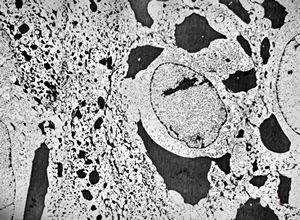

F,64y. | septate junctions between giant multivesicular bodies … uterus, stromal sarcoma